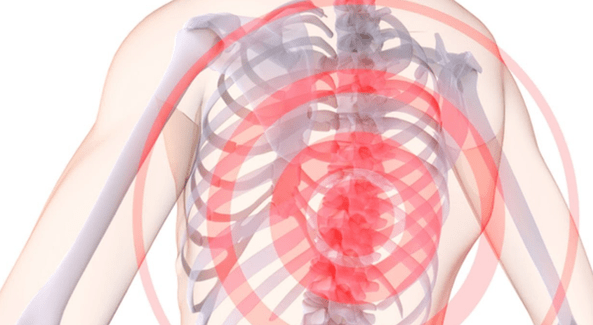

thoracic osteochondrosis ၏လက္ခဏာတွေကဘာတွေလဲ။ ရှေးဦးစွာ ဝေဒနာ ဖြစ်ပေါ်ခြင်း၌၊

- interscapular နှင့် intercostal neuralgic lumbago;

- ရင်ဘတ်၏ဘယ်ဘက်ခြမ်း၌နာကျင်မှု;

- လက်ကို မြှောက်လိုက်တဲ့အခါ လက်ဖျားအထိ နာကျင်လာတယ်၊

- ကွေးသောအခါနာကျင်မှု;

ထို့အပြင်၊ thoracic osteochondrosis သည် ရင်ဘတ်တွင်သာမက ခန္ဓာကိုယ် အစိတ်အပိုင်းများတွင်ပါ ထုံကျင်နေနိုင်သည်ကို ဖော်ပြနိုင်သည်။ တစ်ခါတစ်ရံတွင် osteochondrosis သည် စကားပြောချို့ယွင်းမှုကို ဖြစ်စေပြီး တစ်ခါတစ်ရံတွင် မမြဲသော အရေပြား၊ လက်သည်းများ ကြွပ်ဆတ်ခြင်း၊ ယားယံသော အရေပြားနှင့် အစာခြေစနစ်တို့ကိုပင် ဖြစ်စေသည်။

ရင်သား၏ osteochondrosis နှင့်အတူနာကျင်မှုသည်ကွဲပြားခြားနားသောနည်းလမ်းများဖြင့်သူ့ဟာသူပေါ်လာနိုင်ပါတယ်။ တခါတရံတွင် ယင်းတို့သည် ညနှောင်းပိုင်း၌ ပေါ်လာပြီး ကိုယ်လက်လှုပ်ရှားမှုပြီးနောက် ပျောက်ကွယ်သွားသည့် အပျော့စား ဓားထိုးခြင်း သို့မဟုတ် မှိုင်းမှိုင်းဝေဒနာများဖြစ်သည် - ဥပမာ၊ လမ်းလျှောက်ခြင်းတို. အများအားဖြင့် ကျောရိုးရှိအချပ်ပြားများကို နက်နက်နဲနဲ မထိခိုက်သေးသောအခါ thoracic osteochondrosis ၏ ကနဦးအဆင့်တွင် ဖြစ်လေ့ရှိသည်။

ရောဂါ၏ဖွံ့ဖြိုးတိုးတက်မှု၏နောက်ပိုင်းအဆင့်များတွင်, နာကျင်မှုလက္ခဏာများမကြာခဏသူတို့ကိုယ်သူတို့ lumbago ပုံစံဖြင့်ထင်ရှား။ နာကျင်မှုသည် အသံထွက်သည်၊ စူးရှသည်၊ ပုံမှန်အသက်ရှုခြင်းကို အနှောင့်အယှက်ပေးကာ မလိုအပ်သောလှုပ်ရှားမှုများကိုသာ အခြေအနေပိုမိုဆိုးရွားစေသည်။ မကြာခဏ၊ lumbago သည် အချိန်အတော်ကြာ လှုပ်ရှားမှုမရှိပြီးနောက် စတင်သည် - ဥပမာအားဖြင့်၊ တည်ငြိမ်သောအနေအထားဖြင့် ကွန်ပျူတာတွင် နာရီပေါင်းများစွာ အလုပ်လုပ်ခြင်း။